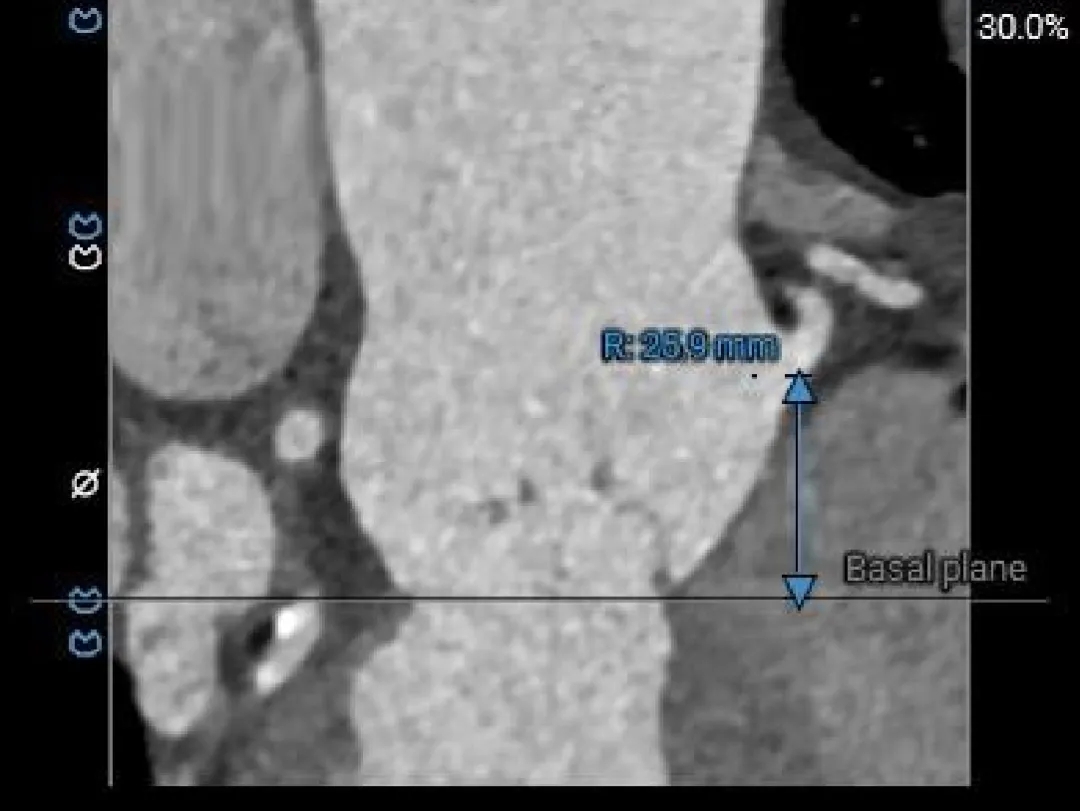

瓣上结构测量

瓣上 2mm

29.9mm

瓣上 4mm

30.2mm

瓣上 6mm

瓣上 8mm

29.5mm